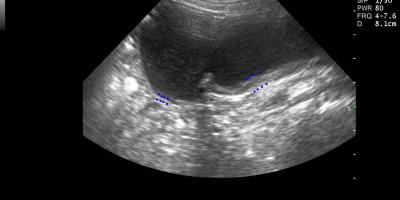

Abdominal Ultrasound, Υπέρηχος κοιλίας CVC infiltration by an adrenal mass in a dog/ Διήθηση της οπίσθιας κοίλης φλέβας από μάζα επινεφριδίου 9 Ιανουαρίου, 2016